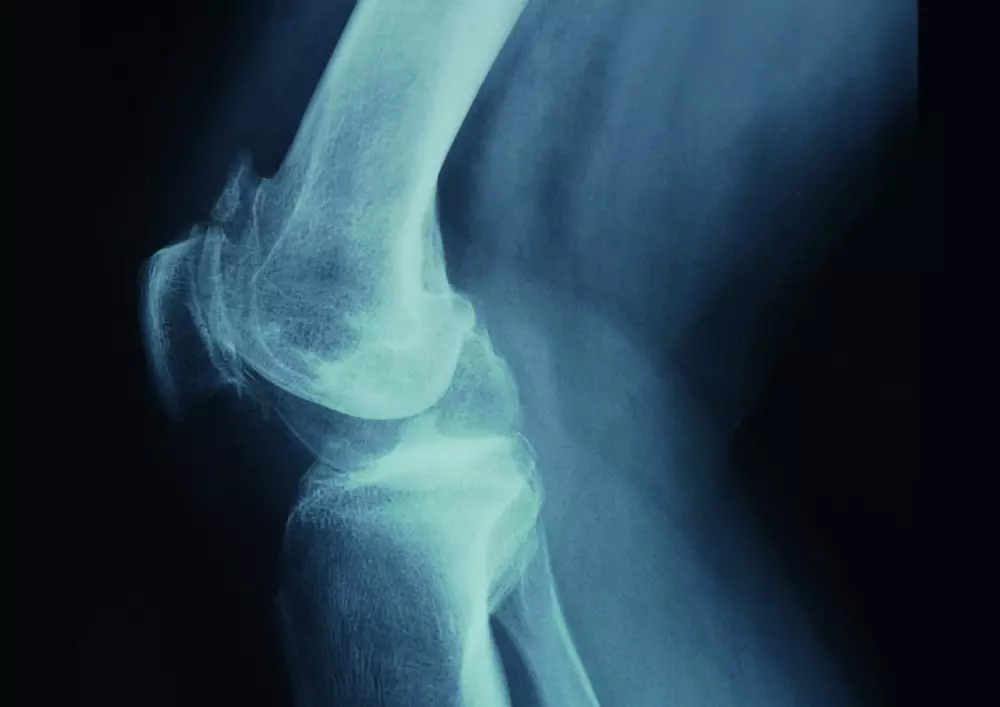

Zachęcamy także do lektury artykułu pt. „Trening propriocepcji po urazach kończyn dolnych”. Wszelkie kontuzje mogą skutkować utratą propriocepcji. Uszkodzenie włókna nerwowego prowadzi do uszkodzenia tkanek miękkich ponieważ mózg nie otrzymuje informacji dotyczącej tego, którą część ciała należy chronić. By temu zapobiec, ważne jest, by wprowadzić trening propriocepcji, który opisujemy w tekście.